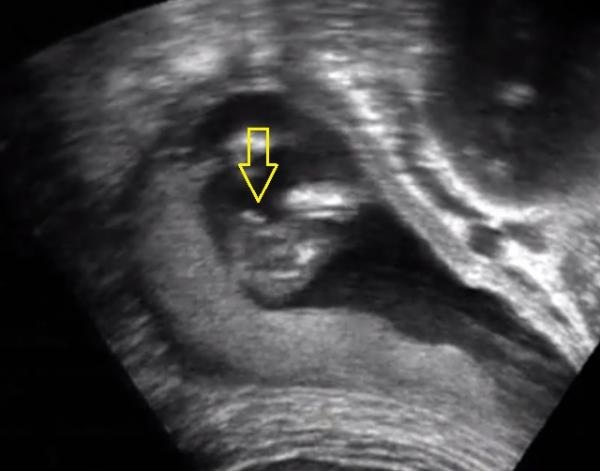

Those are terrible images, I can't even tell they're potty shots. I don't see any gender clues at all. Did the tech say anything?

He leaned girl but he said b previous daughter is a boy, she is all girl! So can I believe him this time?

Here is my scan video, was not for gender determination, but I cannot find boy bits, trying to find them cause swayed strictly boy with MSU !